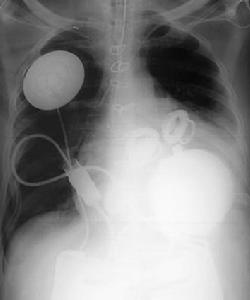

心臟移植手術

移植AbioCor人造心臟的手術極其精密。該過程中,外科醫生不僅要切除和取出原有的左右心室,還要將一個外來物放入胸腔內。患者必須先被放到一台心肺機上,然後再被移走。手術過程中需要縫上數百針,以便將心臟準確固定在人造心室中。移植物將AbioCor與自然心臟的餘下部分相連。移植物是一種合成組織,用於將人造裝置連線到患者的人體組織。

由於手術很複雜,因此有多名醫療人員參與了手術過程。此次移植手術於2001年7月2日進行,在世界同類手術中尚屬首例,參與手術的人員包括2名外科主任醫師、14名護士、灌注師、麻醉師以及其他輔助人員。

外科醫生切除患者自身心臟的左右心室,然後將主動脈和肺動脈置於左右心房中。僅這部分手術就花費了兩到三個小時。

將AbioCor置於胸腔內。外科醫生採用“快速連線器”(類似於小摁扣)將心臟連線到肺動脈、主動脈和左右心房。

此外,這種葡萄大小的裝置必須適合患者的胸腔。為確定裝置是否適合患者,患者必須接受CAT掃描以及X射線胸透。然後,利用一種計算機輔助設計(CAD)程式以虛擬方式切除患者自身的心臟,並以虛擬方式植入AbioCor心臟。如果該電腦程式顯示該裝置正好適合,醫生就可開始移植人造心臟了。手術後近兩個月內,醫院和AbioMed公司的管理人員並未透露首個接受手術的患者姓名。但在2001年8月21日,有訊息透露,這位有史以來首例接受人工心臟移植的人名叫羅伯特·圖爾斯,一名生前在早期電話公司工作的肯塔基州居民。雖然手術後圖爾斯受過感染,並需要通風裝置,但是他的醫生報告說,移植的人造心臟功能一直正常。